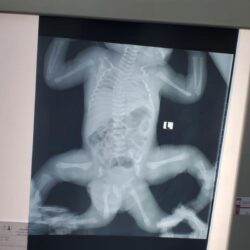

وأضاف الدكتور الربيعة أن التوأم الطفيلي هو عبارة عن طفل مكتمل مع وجود حوض وأطراف سفلية إضافية مزدوجة ومتطفلة على التوأم عائشة وتشترك معها في منطقة الحوض، كما أن هناك عيوبًا خَلقية واشتراك في الجهاز البولي والتناسلي السفلي.